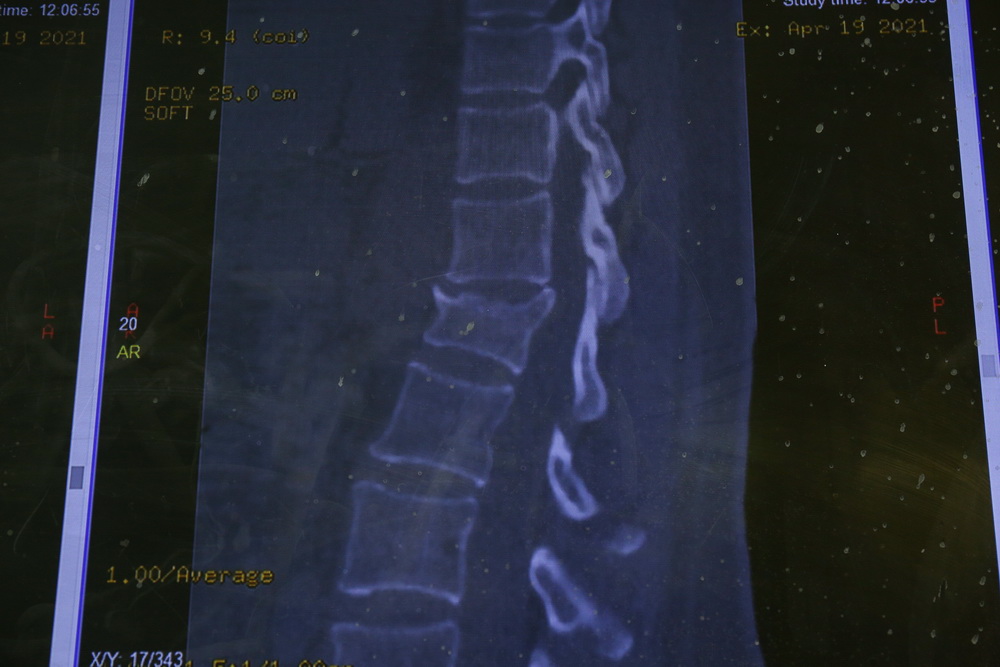

Для начала пациента осматривает бригада специалистов, далее по показаниям проводят дополнительную лучевую диагностику: рентгенографию, МРТ, МСКТ. По снимкам врачи уточняют диагноз и определяют тактику лечения. Не при всех травмах требуется оперативное лечение, только при самых тяжёлых.

Искривление позвоночника ― главный симптом сколиоза. При таком заболевании позвоночник скручивается вокруг вертикальной оси и деформируется во всех трёх плоскостях. В семи из десяти случаев с искривлением сталкиваются девочки.

Перед операцией делают рентген и МРТ позвоночника. После этого врачи определяют тактику процедуры. Во время операции ставят металлическую конструкцию. Её вставляют в позвоночник, а в шурупы вкладывают стержни. Сначала стержни повторяют деформацию, но их разворачивают, и конструкция встаёт по естественным изгибам тела. Потом позвоночник между отдельными шурупами стягивают или растягивают, чтобы он встал ровно.

В конце операции проводят костную пластику ― укладывают собственные кости пациента в зону инструментария. Благодаря этому позвоночник срастается и остаётся прямым. Вся процедура длится четыре часа.